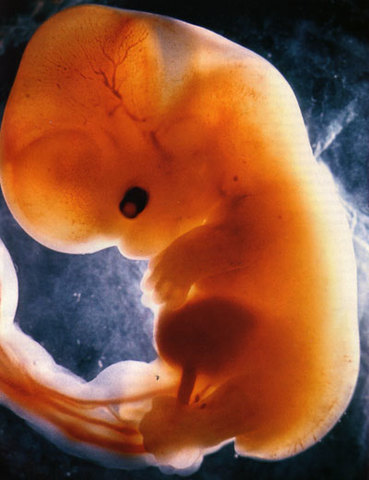

• 3ra semana

3ra semana

el embrión llega a medir 2mm. y la forma del futuro embrión sigue siendo un disco ovalado, pero ya posee tres hojas de tejido (disco embrionario trilaminar).

• primer mes

primer mes

el feto llega a medir 4 mm. y el embrión sigue creciendo